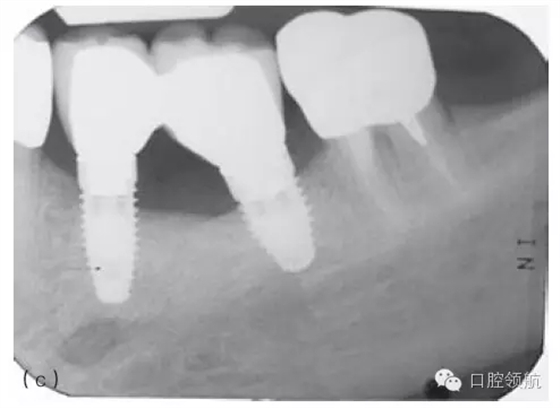

因種植體裝置界面的扭矩可能會(huì)使平臺(tái)連接出現(xiàn)潛在的變形,故應(yīng)注意使該扭矩最小化。Ⅳ類骨植入種植體時(shí)要優(yōu)先在骨上敲打擠壓而不是依靠種植體來(lái)擠壓骨洞。許多廠家會(huì)提醒不要超過(guò)手術(shù)操作時(shí)推薦的扭矩,以減小折斷的可能性(圖5.3a~c)。

圖5.3 (a)Ⅰ類骨中的種植體內(nèi)連接和界面破損的影像學(xué)表現(xiàn)。(b)取出種植體,發(fā)現(xiàn)沿著種植體平臺(tái)的損壞。(c)在重新放置的種植體上行聯(lián)冠修復(fù)完成2年后的影像學(xué)表現(xiàn)。